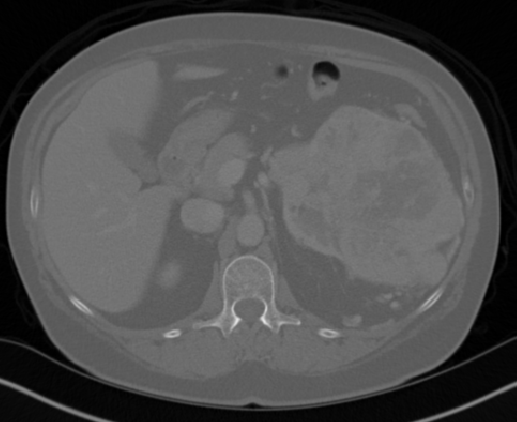

Edge-Aware 3D Image Segmentation Networks

[91]: Automated segmentation of kidneys and kidney tumors is an important step in quantifying the tumor’s morphometrical details to monitor the progression of the disease and accurately compare decisions regarding the kidney tumor treatment. Manual delineation techniques are often tedious, error-prone and require expert knowledge for creating unambiguous representation of kidneys and kidney tumors segmentation. We propose a 3D end-to-end edge-aware FCN for reliable kidney and kidney tumor semantic segmentation from arterial phase abdominal 3D CT scans. Our segmentation network consists of an encoder-decoder architecture that specifically accounts for organ and tumor semantics. We evaluate our model on the 2019 MICCAI KiTS Kidney Tumor Segmentation Challenge dataset. -

Kidney and Kidney Tumor Segmentation

Kidney cancer accounted for nearly 175,000 deaths worldwide in 2018 [13], and it is projected that 14,770 deaths will occur due to the disease in 2019 in the US [111]. Current kidney tumor treatment planning includes Radical Nephrectomy (RN) and Partial Nephrectomy (PN). In RN, both the tumor and the affected kidney are removed whereas in PN the tumor is removed but kidneys are saved [116]. Although RNs were historically prevalent as a standard treatment procedure for kidney tumors, new capabilities for earlier detection of the tumors as well as advancements in surgery has made PNs a viable treatment approach [53].

Traditionally, various techniques such as deformable models [86], GrabCuts, region growing and atlas-based methods have been applied to the problem of kidney segmentation. In recent years, researchers have attempted to leverage the power of deep learning and CNNs to build segmentation frameworks that are more automated and less dependant on incorporation of prior shape statistics. Thong et al. [119] proposed a 2D patch-based approach for kidney segmentation in contrast-enhanced CT scans by leveraging a modified ConvNet.

Jackson et al. [62] developed a framework for detection and segmentation and of kidneys in non-contrast CT images by utilizing a 3D U-Net. Yang et al. [128] proposed a method for kidney and renal tumor segmentation in CT angiography images by a modified residual FCN that is equipped with a pyramid pooling module. Furthermore, Yin et al. [130] employed a cascaded approach for segmentation of kidneys with renal cell carcinoma by training a CNN that predicts a bounding box around the kidney and a subsequent CNN that segments the kidneys. Recently, Xia et al. [126] proposed a two-stage approach for the segmentation of kidney and space-occupying lesion areas by using SCNN and ResNet for image retrieval and SIFT-flow and MRF for smoothing and pixel matching.